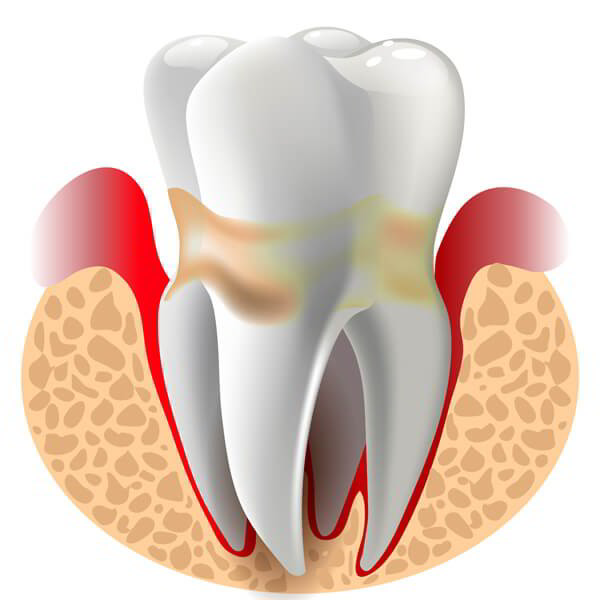

Dental pulp is a small, fibrous tissue between teeth. The main cause of dental pulp damage is tooth decay or dental wounds. When not…